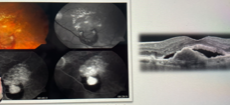

membrana epirretiniana distorcendo o contorno macular

síndrome de tração vítreo-retiniana